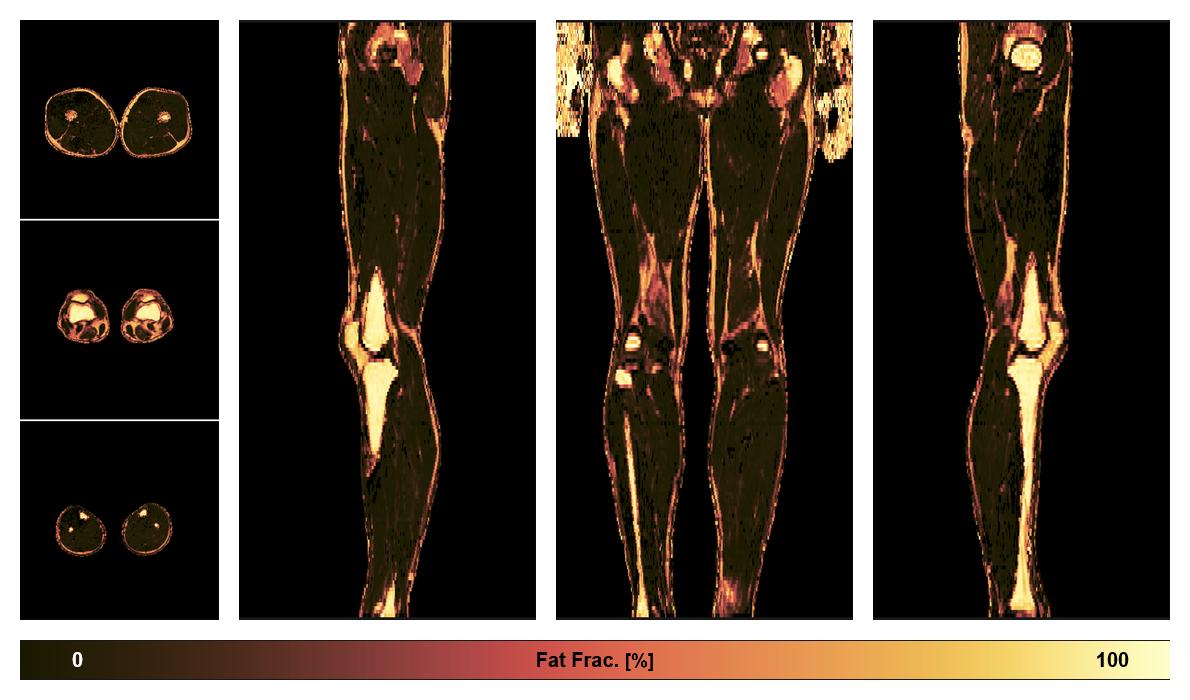

• Fat fraction

The fat fraction of the lower extremity obtained from the dixon reconstruction for muscle water fat quantification.